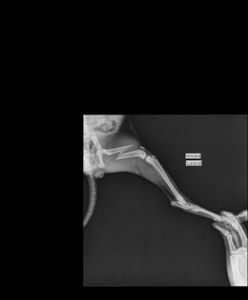

Na manhã seguinte, dia 11/08/2021, levei na clínica veterinária da Unama e fizemos um raio x onde foi identificado uma fratura no fêmur esquerdo. Infelizmente, a clínica da unama não realiza cirurgia ortopédica e foi necessário entrar em contato com um veterinário particular.  Ao repassar o caso, tivemos um orçamento da cirurgia de R$1.600,00, e mais a internação que custa R$120,00 a diária. Entretanto, ao implorar por desconto, consegui a cirurgia por R$1.400,00 á vista ou R$1.600,00 no cartão. Já conseguimos alguns dias de internação grátis, mas necessitamos desse valor para realizar o proedimento e os demais cuidados pós operatório.